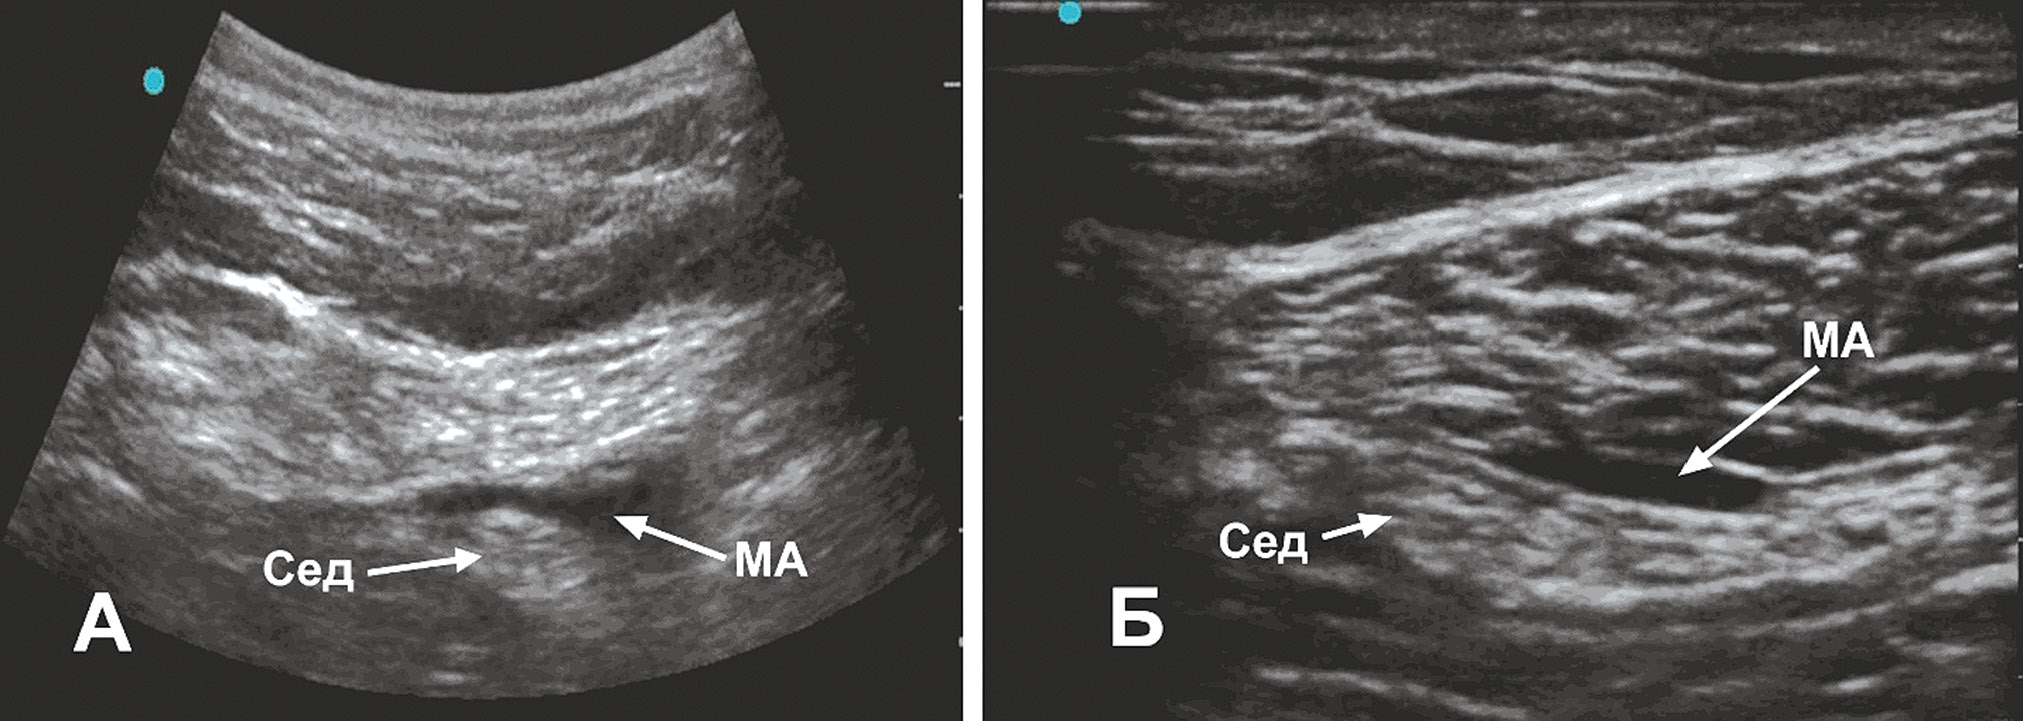

В послеоперационном периоде у одного пациента через 15, у другого через 18 ч произошло восстановление моторной и сенсорной функций в зоне иннервации бедренного нерва. В зоне иннервации седалищного нерва продолжал сохраняться полный моторный и сенсорный блок. Пациенты были осмотрены неврологом, выполнено ультразвуковое исследование места блокады. При ультразвуковом исследовании у обоих пациентов выявлено сохранение облака анестетика, расположенного рядом с седалищным нервом. На рисунке 2, А представлена ультразвуковая картинка через 18 ч после блокады, виден гипоэхогенный слой местного анестетика. На сонограмме, выполненной через 26 ч (рис. 2, Б), слой анестетика уменьшился и сместился более дистально.

Рис. 2. Ультразвуковое исследование со стороны задней поверхности бедра. А – сканирование через 18 ч после блокады. Б – через 26 ч после блокады (Сед – седалищный нерв, МА – местный анестетик)

Fig. 2. Ultrasound examination from the back of the thigh. A – Scan 18 hours after the blockade. Б – 26 hours after the blockade (Сед – sciatic nerve, MA – local anesthetic)

Выявленное через 18 ч депо местного анестетика рядом с седалищным нервом позволило предположить продлённую анестезию седалищного нерва вследствие замедления скорости резорбции левобупивакаина. На снижение скорости резорбции могло повлиять несколько факторов. Первый – это возраст пациентов, влияющий на перфузию тканей за счёт возрастных изменений. Второй фактор – это сам анестетик левобупивакаин, обладающий вазоконстрикторными свойствами [11, 12]. Третий фактор – это место введения: при ультразвуковом исследовании было обращено внимание, что параневральное пространство, куда был подведён анестетик, выглядело как обеднённая сосудистая зона. По нашему мнению, именно совокупность этих факторов оказала влияние на длительное депонирование анестетика в параневральном пространстве и длительную анестезию седалищного нерва.